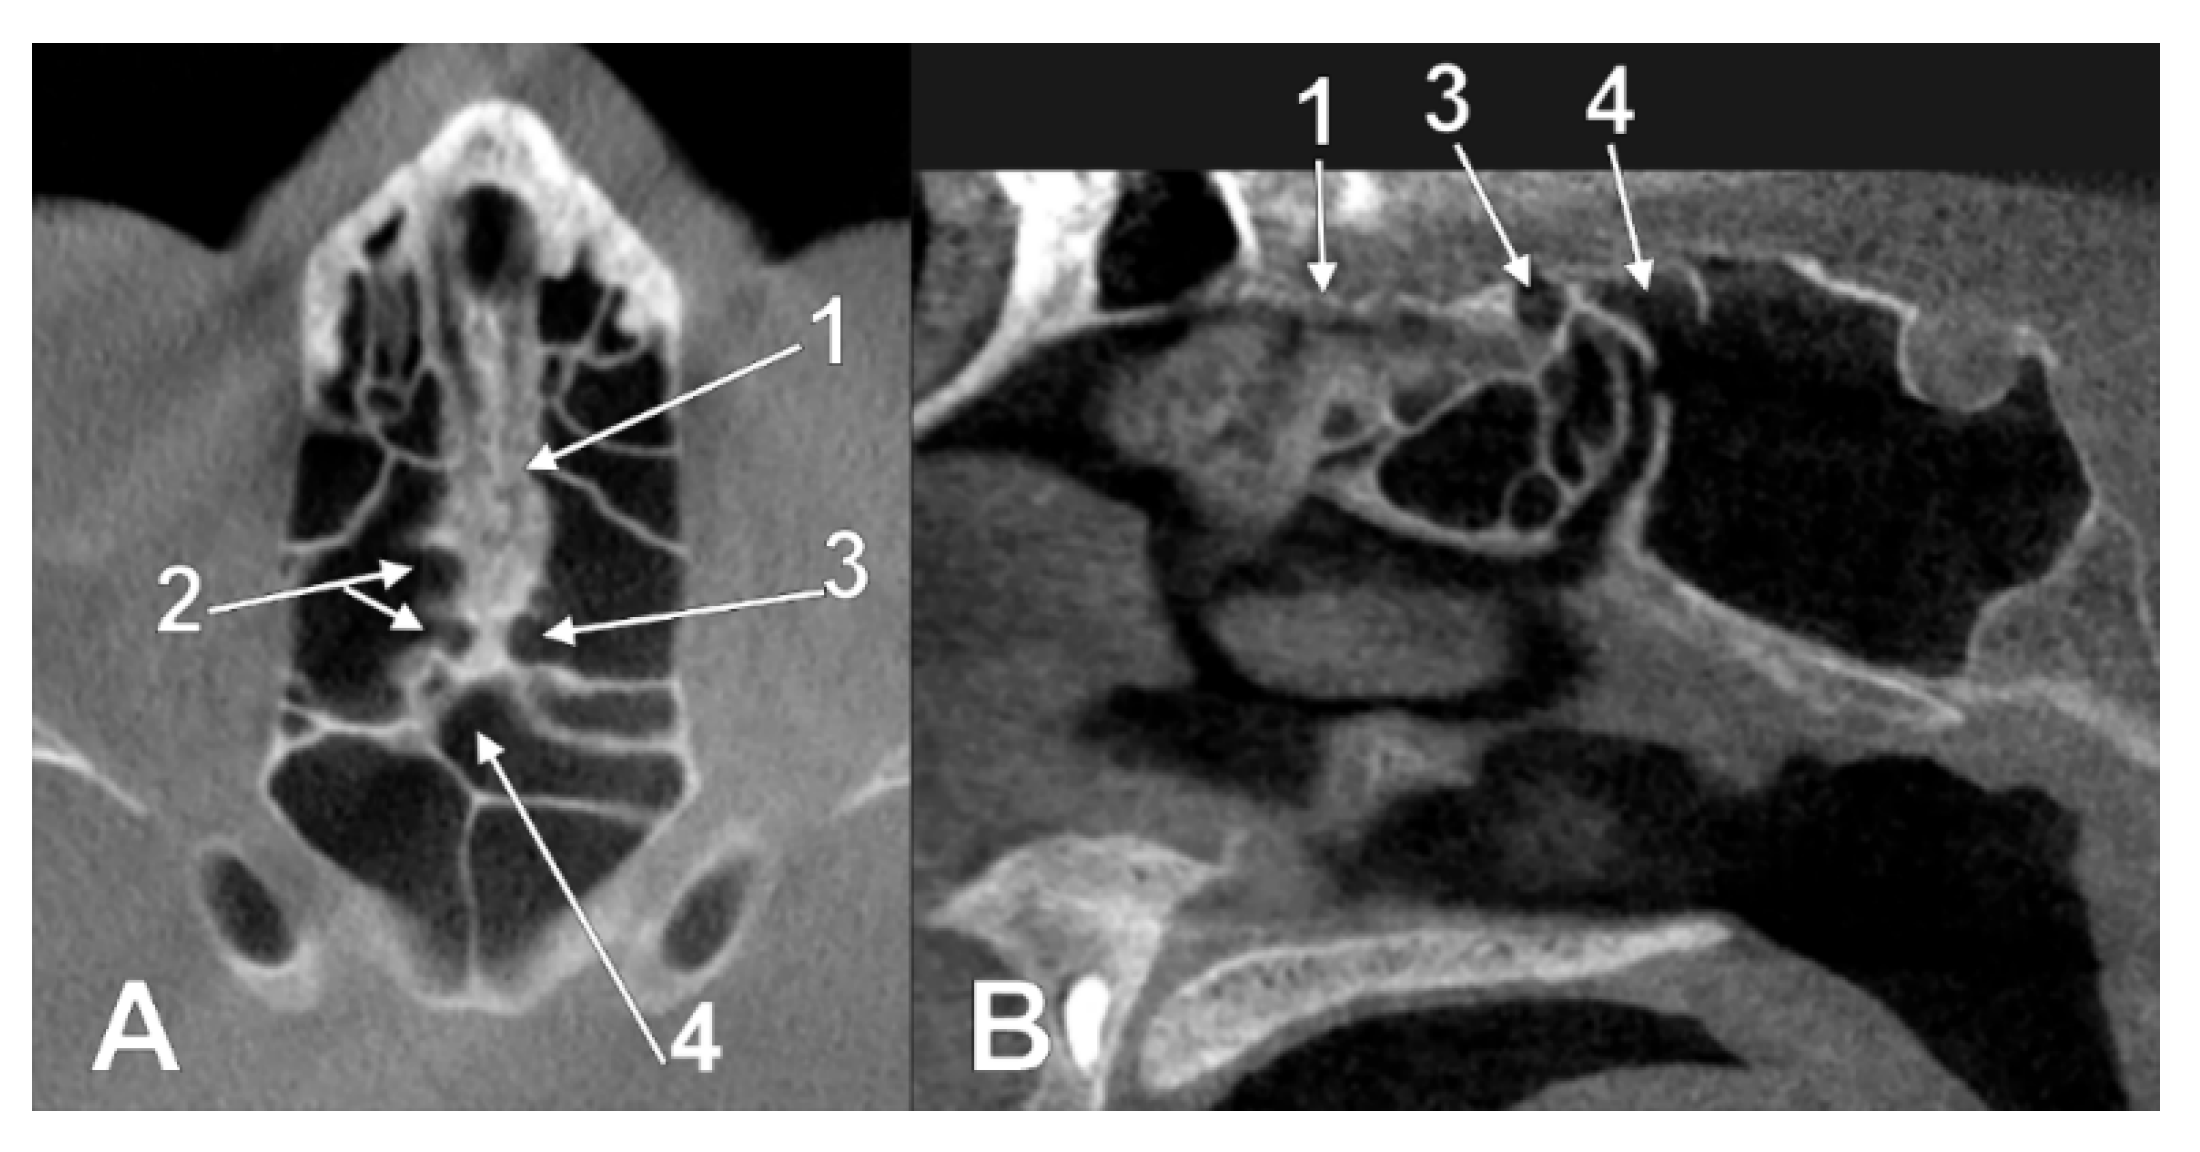

3.1. Ethmoidal Origin of Nasal Roof Pneumatizations

3.2. Sphenoidal Origin of Nasal Roof Pneumatization